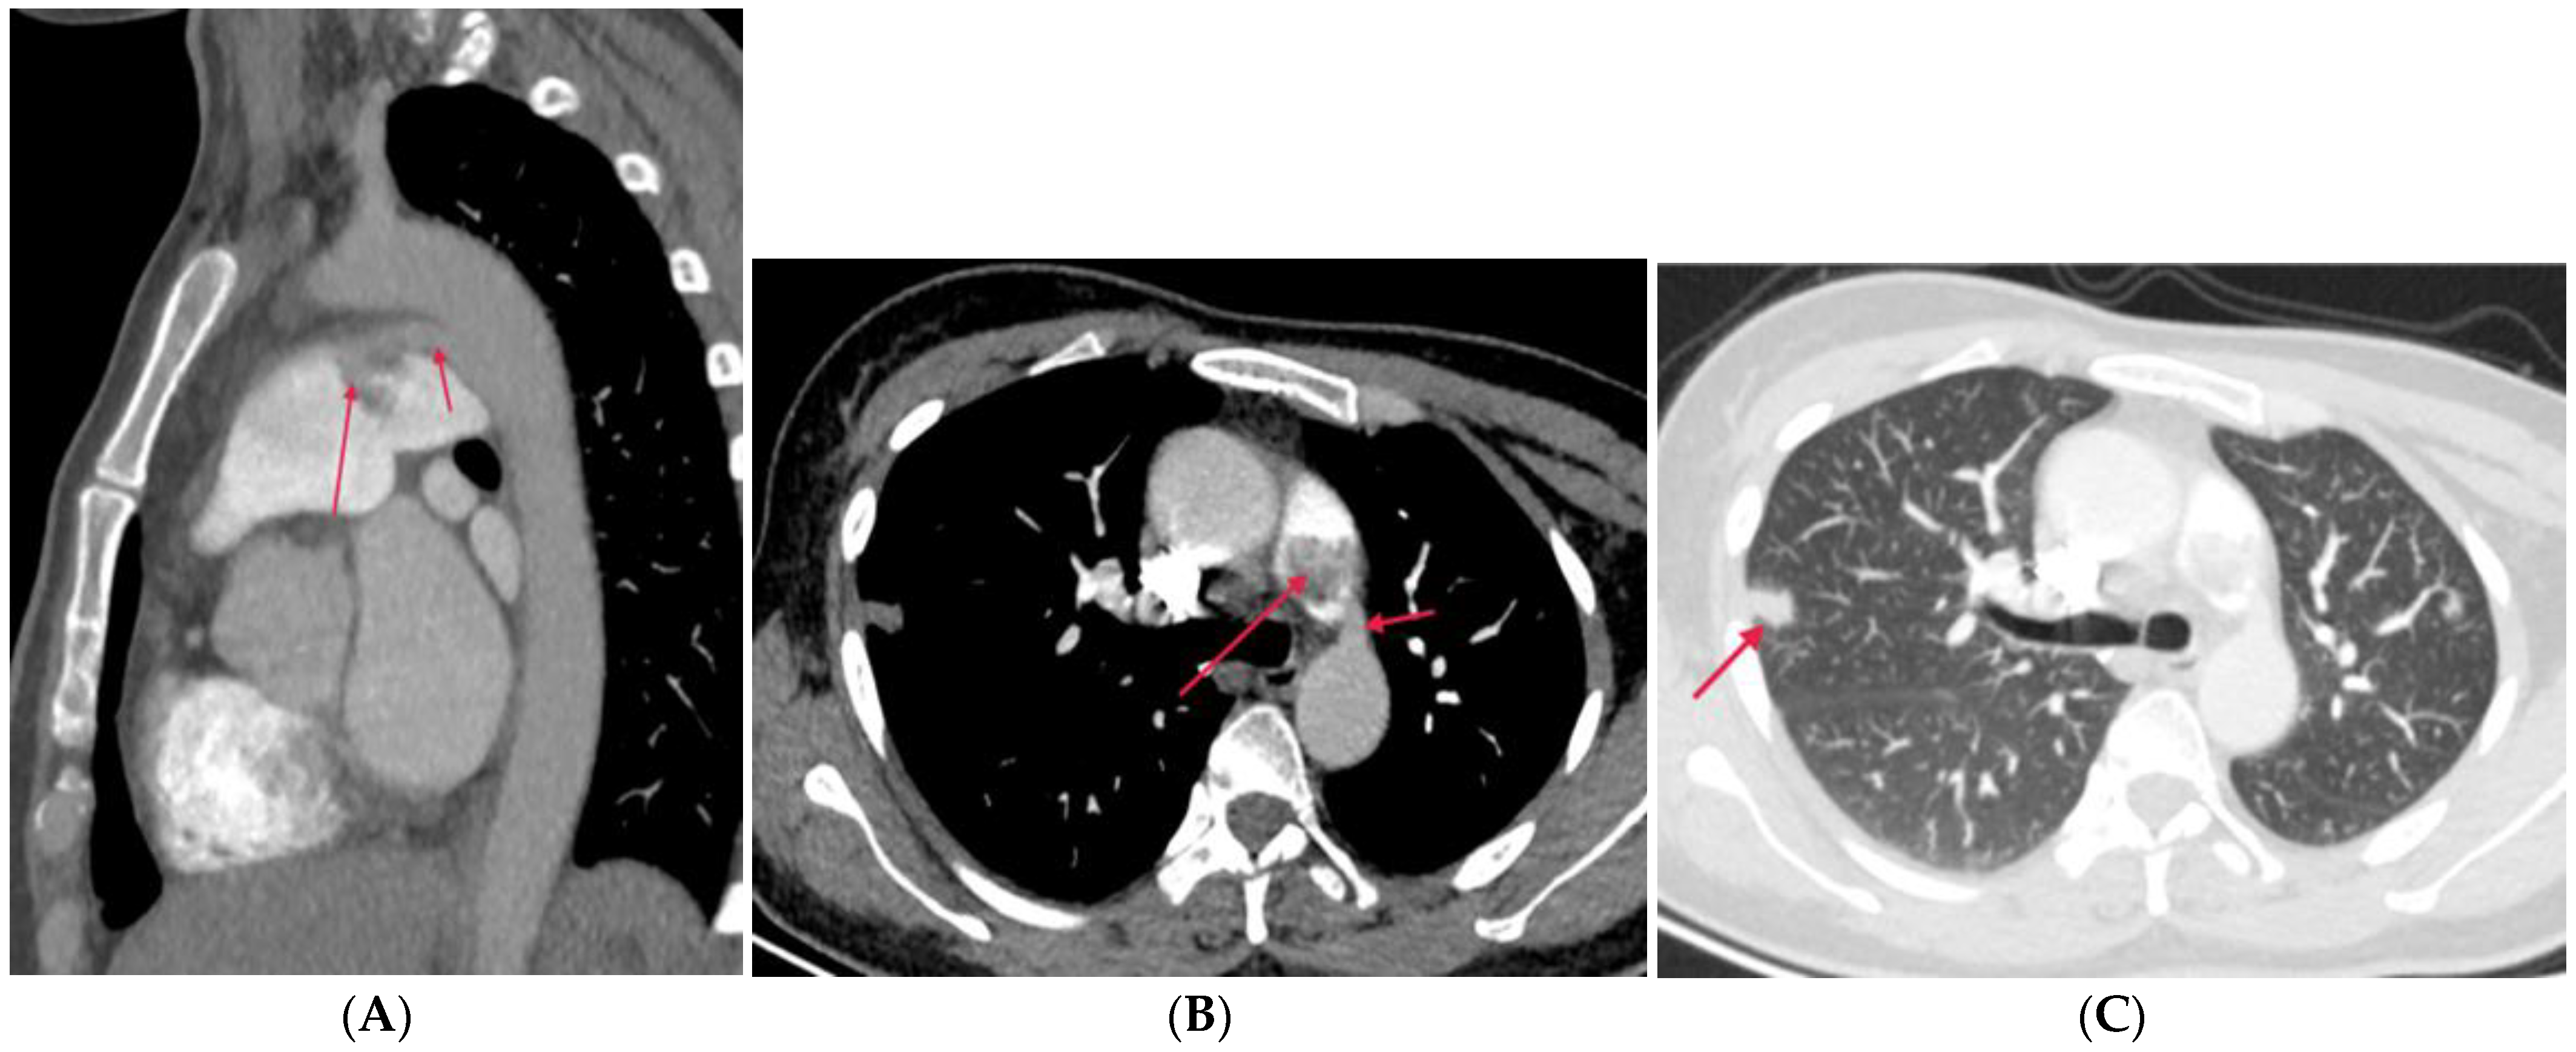

4.2.1. Takayasu Arteritis (TA)

4.2.2. Behçet Disease (BD)

4.2.3. Swyer–James–Macleod Syndrome (SJMS)